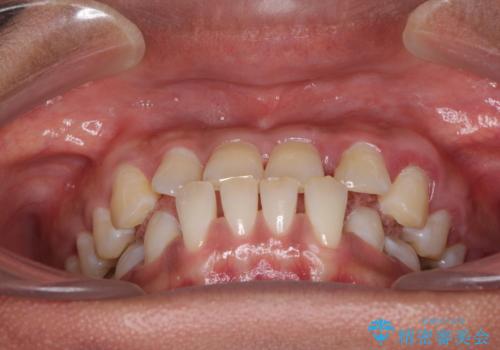

- 前歯の隙間と反対咬合を気にして来院された患者様です。

咬合力が強く、反対咬合の改善に時間がかかりましたが、その後はスムーズに進めることができました。